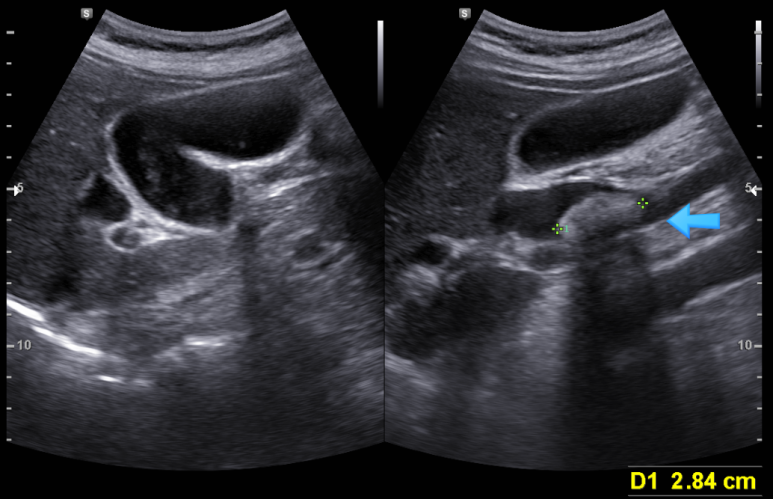

수동 혈압 측정시 불규칙한 맥박이 의심되어 확.. : 네이버블로그 상기 환자 2월에 심초음파 이 당시도 심전도에서 심방세동 상태 다른 소견은 없으나 좌심방의 AP diameter는 3.93 cm, volumn은 54.3 ml/m2 으로 부피...